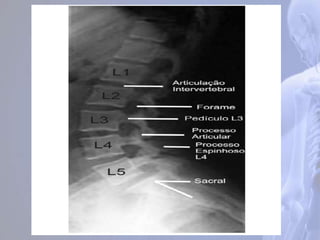

Região Lombar (LI – LV)

São as maiores e mais fortes da coluna.